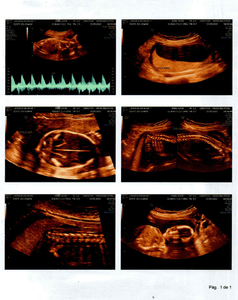

Olá amigos e amigas, eu Laidson Saturnino Souza Santos, descobri que minha filha, com idade gestacional de 21 semanas e 6 dias, foi diagnosticada com MIELOMELINGOCELE SACRAL, ESPINHA BÍFIDA OU ESPINHA ABERTA, no dia 13/09/2022, por meio de uma ultrassonografia morfológica. Ela possui uma MALFORMAÇÃO NA COLUNA. Em decorrência disto provavelmente nascerá com ANOMALIAS ESTRUTURAIS, DOENÇAS GÊNICAS, RETARDO MENTAL, CROMOSSOMOPATIAS (SINDROME DE DOWN), entre outros problemas. A única forma de tentar reverter esse problema seria uma cirurgia intrauterina, ou seja, os médicos farão uma cesárea, irão abrir o útero da mãe, chegar até meu filho, onde irão fechar a sua coluna, q está aberta. Feito isto suas chances de nascer perfeito São grandes, claro que os médicos não descartam a hipótese de haver sequelas, mas acreditamos na cura total. Se a mãe não se submeter a esse procedimento, assim q ela nascer irá pra cirurgia para fechar a coluna, mas já será tarde demais e consequentemente ficará sem andar entre outras complicações e por fim será uma menina especial pro resto da vida. Estamos aqui correndo contra o tempo, pois o prazo será até a 26ª semana, ou seja, temos 4 semanas para organizar tudo, e levantar o dinheiro. Não sabemos ao exato o quanto custa essa cirurgia, mas passa de $ 20,000 DÓLARES, aqui no Brasil. Onde moramos, Bahia, este procedimento não é realizado, só em São Paulo ou Rio de Janeiro. Então abandonaremos tudo aqui, família, amigos, ...  para tentar dar um futuro melhor para a LIZ. Estamos tentando os órgãos públicos para obtermos a cirurgia através do SUS (Sistema Único de Saúde). Mas é difícil e não temos como esperar. Então criamos uma conta para levantarmos a quantia suficiente e assim poder realizá-la. Peço que quem tiver interesse em ajudar repasse esta mensagem aos seus amigos, para juntos salvarmos a vida da minha menina.